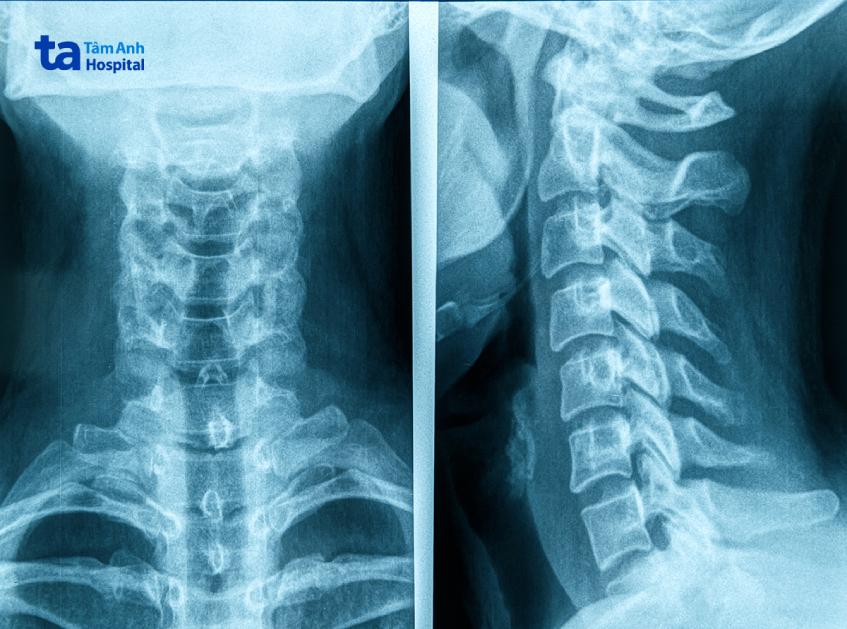

Chụp X quang cột sống cổ giúp tạo nên hình ảnh giải phẫu 7 đốt sống đầu tiên của cột sống. Hình ảnh X quang cột sống cổ giúp bác sĩ đưa ra chẩn đoán về những chấn thương hoặc bệnh lý tại cột sống cổ.

Kỹ thuật X quang cột sống cổ sẽ chụp tổng cộng 7 đốt sống cổ (7 đốt sống đầu tiên của cột sống). Ảnh phim X-quang cột sống cổ sẽ giúp bác sĩ quan sát cấu trúc các đốt sống cổ và mô mềm xung quanh khu vực này.

Hình ảnh X-quang cột sống cổ bình thường sẽ thể hiện:

Hình ảnh X-quang cột sống cổ bất thường sẽ thể hiện: